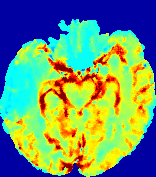

LesionRefer to captionRefer to captionRefer to captionRefer to captionRefer to captionRefer to caption𝐕rgbsubscript𝐕𝑟𝑔𝑏{\bf{V}}_{rgb}Refer to captionRefer to captionRefer to captionRefer to captionRefer to captionRefer to caption𝐕2subscriptnorm𝐕2{\|\bf{V}}\|_{2}Refer to captionRefer to captionRefer to captionRefer to captionRefer to captionRefer to captionRefer to caption3.53.53.52.82.82.82.12.12.11.41.41.40.70.70.70.00.00.0(mm/s)𝑚𝑚𝑠(mm/s)D𝐷DRefer to captionRefer to captionRefer to captionRefer to captionRefer to captionRefer to captionRefer to caption0.0200.0200.0200.0160.0160.0160.0120.0120.0120.0080.0080.0080.0040.0040.0040.0000.0000.000(mm2/s)𝑚superscript𝑚2𝑠(mm^{2}/s)Slice #1Slice #2Slice #3Slice #4Slice #5Slice #6

Figure 4: PIANO feature maps for another patient in the ISLES 2017 training set, where the lesion is located in the right hemisphere. Top row: segmented stroke lesion region (white) on different slices. The corresponding slices for the PIANO feature maps are shown in the following rows.

For a better insight into an estimated velocity field 𝐕𝐕{\bf{V}} and diffusion field 𝐃𝐃{\bf{D}}, we compute the following maps: (1) 𝐕rgbsubscript𝐕𝑟𝑔𝑏{\bf{V}}_{rgb}: Color-coded orientation map of 𝐕=(Vx,Vy,Vz)T𝐕superscriptsuperscript𝑉𝑥superscript𝑉𝑦superscript𝑉𝑧𝑇{\bf{V}}=(V^{x},V^{y},V^{z})^{T}, obtained by normalizing 𝐕𝐕{\bf{V}} to unit length and mapping its 3 components to red, green, blue respectively; (2) 𝐕2subscriptnorm𝐕2\|{\bf{V}}\|_{2}: 222 norm of 𝐕𝐕{\bf{V}}; (3) D𝐷D: scalar field in Eq. 5.

Fig. 3 and Fig. 4 show the PIANO feature maps estimated from two ISLES 2017 patients: all are highly consistent with the lesion in both cases. Details of the blood flow trajectories are revealed in 𝐕rgbsubscript𝐕𝑟𝑔𝑏{\bf{V}}_{rgb} by the ridged patterns and the sharp changes of colors in the unaffected (right) hemisphere, while the flat patterns appearing within the lesion provide little directional information about the velocity and indicate low velocity magnitudes. Velocity magnitudes are more directly visualized via 𝐕2subscriptnorm𝐕2\|{\bf{V}}\|_{2}, from which one can easily locate the lesion where 𝐕2subscriptnorm𝐕2\|{\bf{V}}\|_{2} is low. D𝐷D also indicates lower diffusion values in the lesion, though with less contrast potentially due to the fact that it captures the accumulated effect of CA diffusion at the voxel-level.